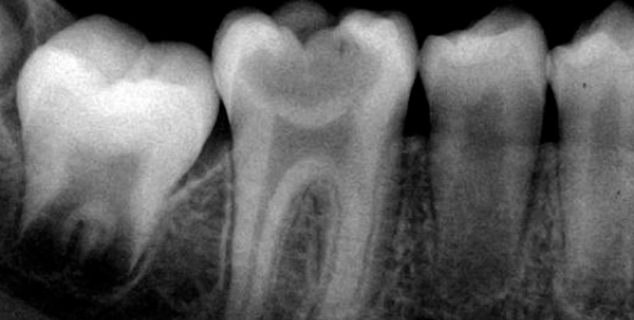

• Радиовизиограф позволяет выявить количество, длину, строение каналов, качество их прочистки, плотность заполнения пломбировочным составом.